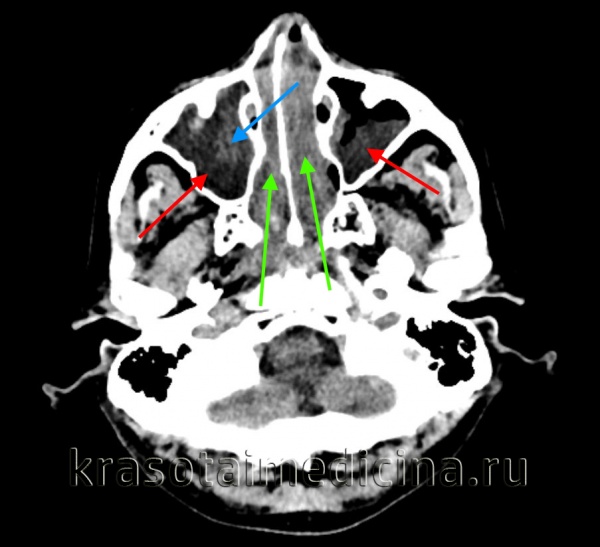

КТ ППН. Этот же пациент. Диффузное снижение пневматизации ячеек решетчатого лабиринта (синяя стрелка), гиподенсный отек слизистой оболочки сфеноидальных пазух (красная стрелка).